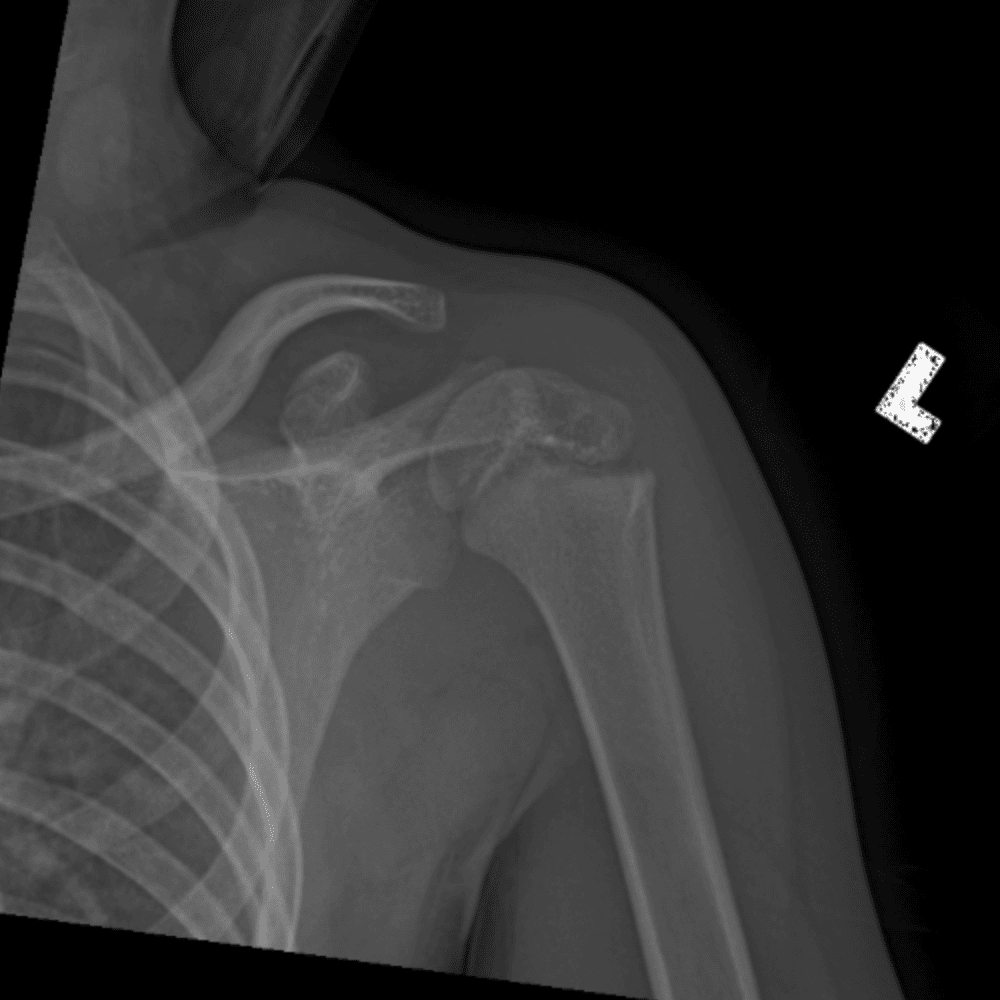

Simuliert den Dienst durch subtile oder schwierige Fälle und einige Normalbefunde.

30 Fälle